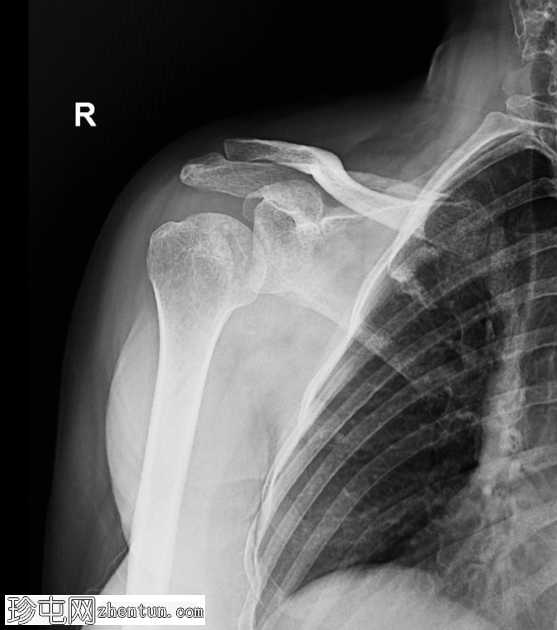

轴位片

肱骨头向后移位至肩胛盂后方,证实肩关节后脱位。现有

影像

未见明确的相关骨折。

轴位片(或肩胛Y形位)对于确认后脱位至关重要。